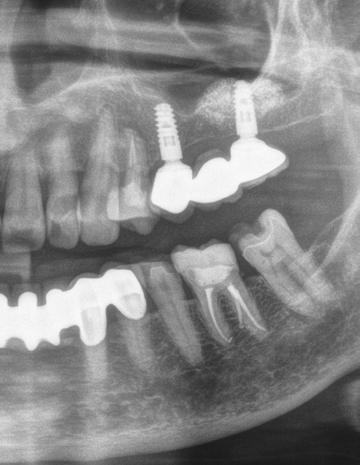

A korai harmicas éveiben járó hölgy rendelőnkbe érkezésének oka a jobb felső nagymetsző fog bizonytalan érzkenysége, elmondása alapján gyermekkorában trauma érte a felső frontrégiót. A frakturált klinikai koronákat kompozittöméssel helyreállították, egyéb kezelést akkor nem tartottak szükségesnek. Az utóbbi hónapokban tapasztalt érzékenység miatt kereste fel rendelőnket. A klinikai vizsgálat (1. és 2. kép) és a CBCT felvétel (3. kép) alapján diagnosztizált külső gyökérreszorpció megoldására a fog eltávolítását, implantátum

bukkális 1. kép: Kiindulási állapot, 2020. január. 3. kép: Kiindulási CBCT felvétel. 2. kép: Kiindulási állapot a palatinális oldal felől.

1. ábra: Megfelelő szájhigiénia – panorámaröntgen. 2. ábra: A 2.5, 2.6 és 2.7-nek megfelelő terület a röntgenfelvételen.

és jelentős mobilitással rendelkezett. A radiológiai vizsgálat után egyértelműen látszódott, hogy a fogon még nem végeztek gyökérkezelést. A 2.6-os és 2.7-es fogaknak megfelelő területen az arcüreg kiterjedése jelentős volt, vertikális csontmennyiség szignifikánsan csökkent (1. és 2. ábra).